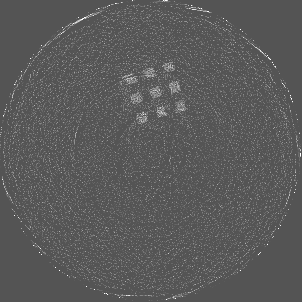

Figure 7 shows a single slice spectral reconstruction of the Mg scaffold. Due to low atomic number of Mg (Z = 12) compared to Ti (Z = 22), the results did not exhibit any significant beam hardening effects. Low energy reconstruction shows good spatial information while high energy ranges are limited by photon noise. In scans involving smaller samples made from low-Z materials like Al or Mg, acquiring low energy quanta in CSM provide high spatial information with minimum or no beam hardening effects. Figure 8 illustrates a single slice spectral reconstruction of the Ti mesh. Similar to the Ti scaffold, streaks are less pronounced in the mid and high energy ranges.

Refer to caption

(a) 15 to 80 keV

(b) 35 to 80 keV

(c) 55 to 80 keV

(d) 62 to 80 keV

Figure 7: Spectral reconstruction of Mg scaffold. Low energy ranges provide good spatial resolution while high energy ranges are limited by photon noise.